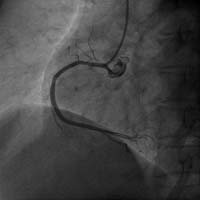

右冠狀動脈閉塞 介入術后右冠開通